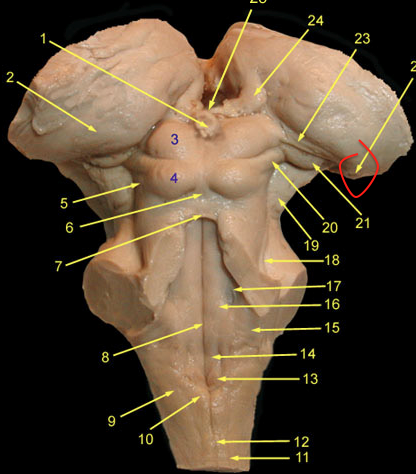

prectum

superior colliculis

occulomotor

occulomotor nerve

lateral geniculate n.

MGN

input - inferior colliculus

output - hescl’s gyrus

Vestibulo-cochlear Nerve

what does the lateral lemniscus carry?

from cochlear n. to the inferior colliculus